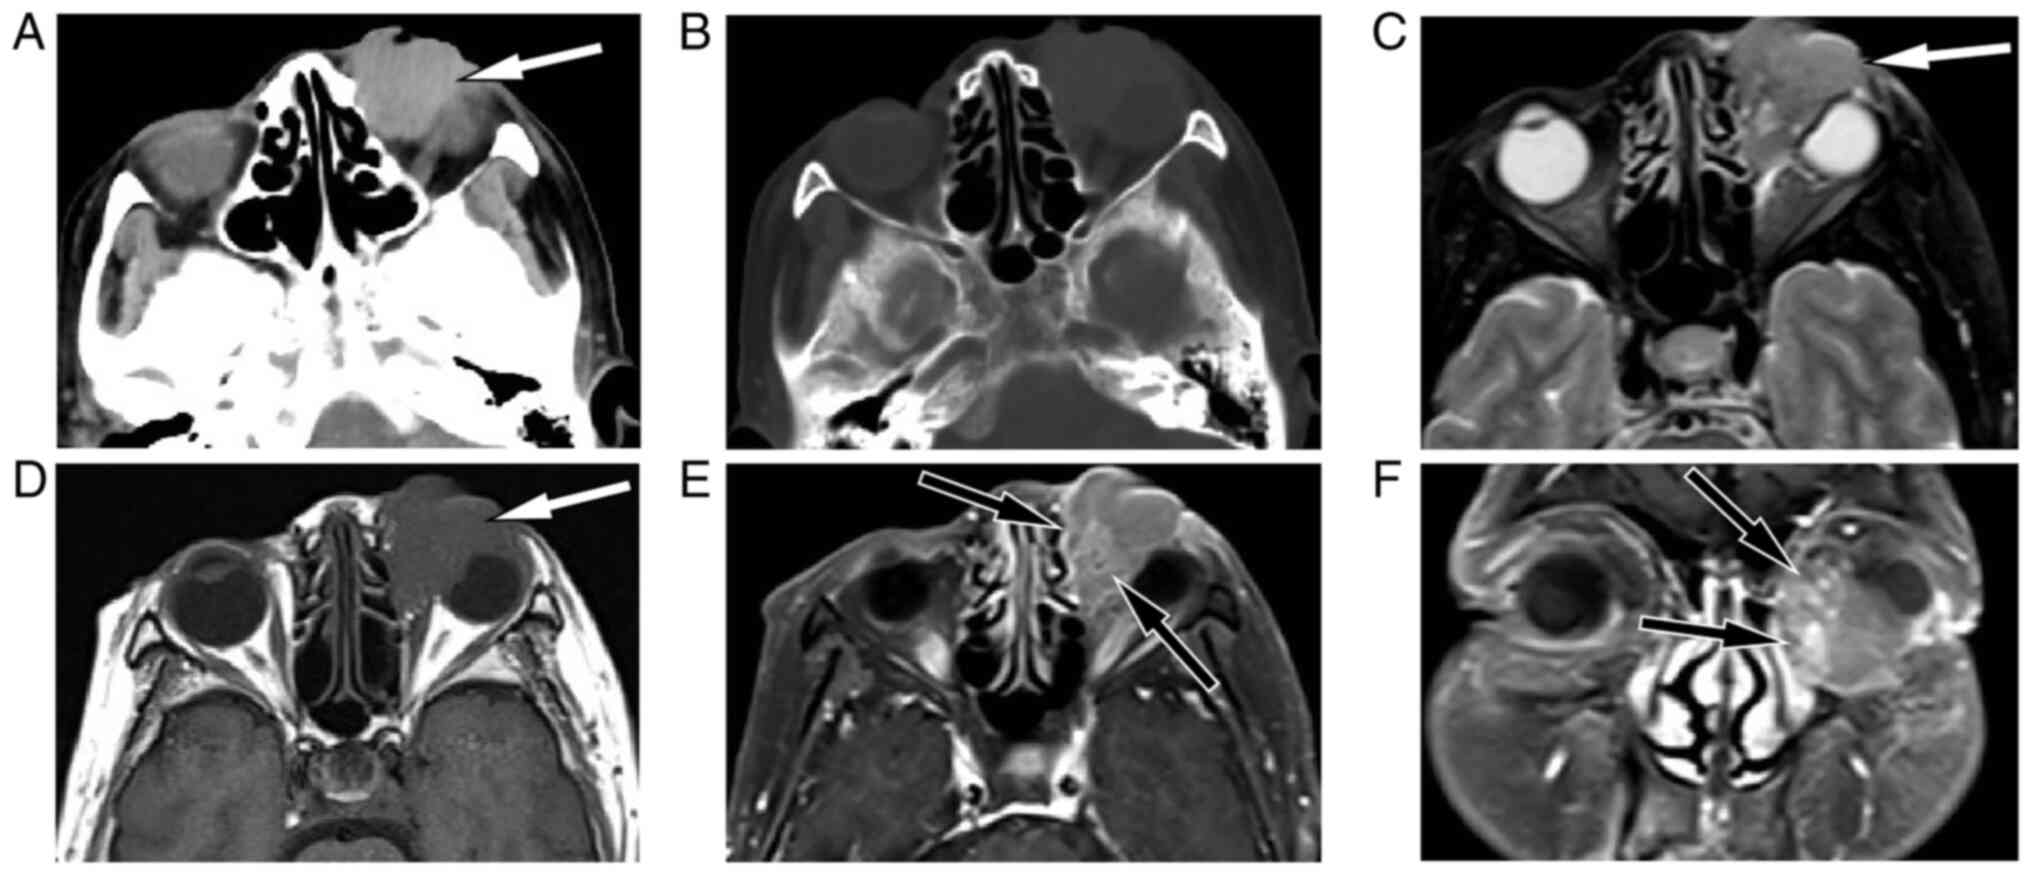

Figure 1.

(A) Head CT showed a slightly hyperdense mass measuring ~2.8×2.4 cm outside the left orbital muscle cone (white arrow), and the left eyeball showed pressure changes. (B) The CT bone window showed no obvious signs of bone resorption or bone destruction in the adjacent bone. (C) T2WI sequences of magnetic resonance imaging showed the lesion to be slightly hyperintense (white arrow). (D) T1WI sequences showed the lesion to be of equal signal with soft tissue (white arrow). (E) Axial and (F) coronal contrast-enhanced T1WI sequences showed inhomogeneous enhancement of the lesion, with markedly enhanced tortuous vascular shadows (black arrows) seen within the tumor tissue. CT, computed tomography; WI, weighted imaging.